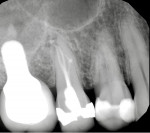

The clinical examination revealed severe pain to percussion and biting as well as vitality testing showing tooth No. 4 to have a necrotic pulp. Periodontal examination produced no pathologic pocketing or mobility. Upon examination of the digital radiograph in the region of the patient's pain, a periapical radiolucency was found associated with tooth No. 4 (Figure 1). A cone-beam computed tomography (CBCT) scan also confirmed the periapical pathology, as well as tooth No. 4 exhibiting three roots/canals (Figure 2 and Figure 3).